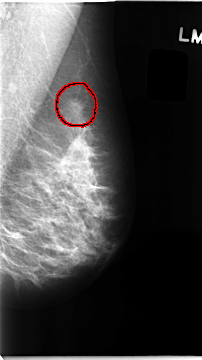

C_0097_1.LEFT_CC

LEFT_CC LINES 4728 PIXELS_PER_LINE 2640 BITS_PER_PIXEL 12 RESOLUTION 50 OVERLAY

FILE: C_0097_1.LEFT_CC.OVERLAY

TOTAL_ABNORMALITIES 1

ABNORMALITY 1

LESION_TYPE MASS SHAPE IRREGULAR MARGINS SPICULATED

ASSESSMENT 5

SUBTLETY 5

PATHOLOGY MALIGNANT

TOTAL_OUTLINES 1

BOUNDARY